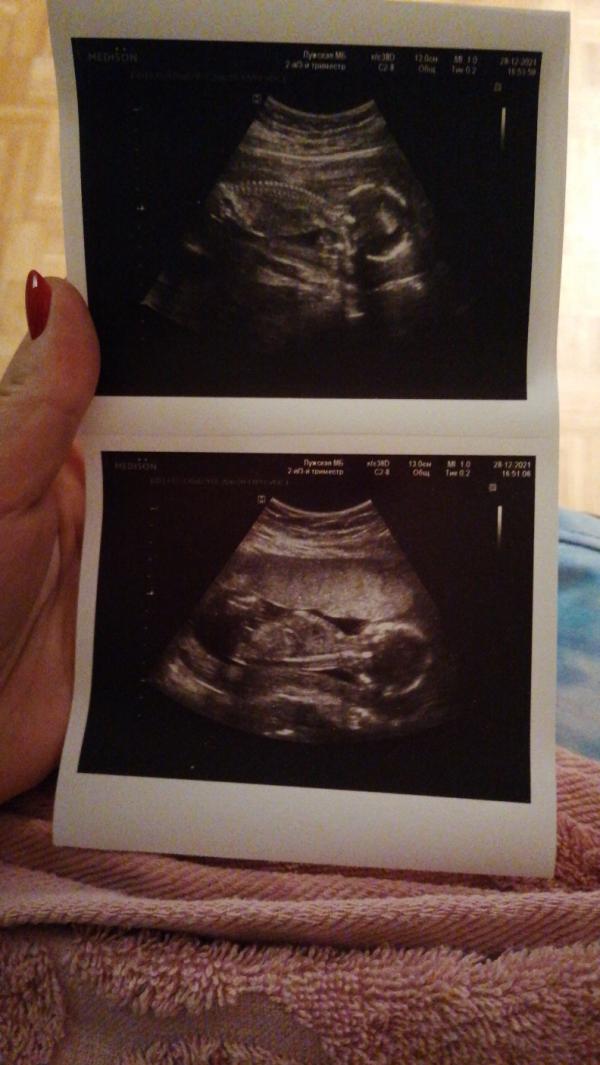

Сейчас пошла 19 неделя, а я только на 17 узнала, что беременна. Врачи кто смеялся, кто ругался, но в общем были в шоке "как можно так долго ходить, не замечая🤭" Друзья тоже в шоке. Дело в том, что неспроста же 12 лет без детей, куча больниц и врачей, диагноз бесплодие. Были и сопутствующие болезни: воспалительные (оофорит, аднексит, кисты и много всего😔) прогестерон 0,4, что очень мало. Удалена левая труба в результате внематочной беременности. Цикл сбит, менструации шли раз в 2-3 месяца, поэтому на задержки не обращала внимания🥴 из-за хронического цистита не придала значения частым похода в туалет😁 а из-за гастрита и язвы не обращала внимания на тошноту и рвоту, тк привычное явление. В аптечке всегда валялся тест, периодически делала "А ВДРУГ" но все было безрезультатно. И вот 27 декабря, в который раз делаю тест и... 2полоски!!! Девчули, руки тряслись, радости не было предела, слезы рекой. Побежала в аптеку, купила ещё 2 теста других фирм- все подтвердились! На след. утро пошла в ЖК. Не верила до последнего, тк однажды мне в женской врач сказала, что беременна, а по УЗИ оказалось просто большая киста🙈 Слушая сердечко плакала, но все же не верила. Ждала УЗИ. И вот мой снимок! Оболдела, увидев рёбрышки, позвоночник, ручки и ножки😭 сказали пол) предположительно пока, тк ножки скрещены)